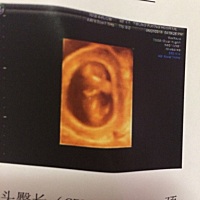

能看出来是男孩还是女孩吗